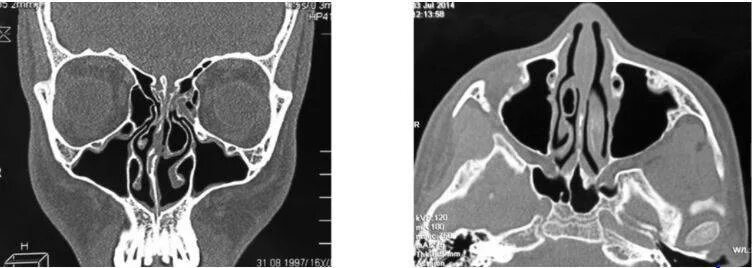

Кт онп что это